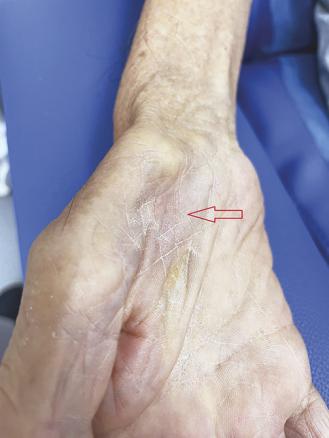

L’examen note une pression artérielle à 130/81 mmHg, la marche est normale, avec un balancement des membres supérieurs, il existe une hypertonie diffuse sans roue dentée. Des fasciculations sont observées au niveau des membres inférieurs. Les réflexes ostéotendineux sont très vifs aux quatre membres. Il existe une amyotrophie du court abducteur du pouce (fig. 1) et des interosseux dorsaux, prédominant sur le premier interosseux (fig. 2), avec perte de la pince pouce-index. L’abducteur du cinquième doigt est relativement épargné.

Évoqué par l’examen clinique, le diagnostic de sclérose latérale amyotrophique est confirmé par un électromyogramme qui élimine une neuropathie à bloc de conduction, et met en évidence des signes de dénervation dans les quatre membres. Les amplitudes des réponses motrices sont effondrées pour le court abducteur du pouce et préservées pour l’abducteur du cinquième doigt.

Décrit à la fin du siècle dernier par Wilbourn,2 le split hand sign désigne une atrophie du bord latéral de la main portant sur l’éminence thénar et le premier interosseux dorsal, et respectant la loge hypothénarienne. Les muscles atteints dans le split hand sont innervés par le même segment médullaire cervical C8-T1 ; les muscles premier interosseux

et abducteur du cinquième doigt, qui sont différemment touchés, sont tous deux innervés par le nerf ulnaire. Le mécanisme physiologique sous-tendant ce phénomène est incomplètement élucidé, une origine corticale ou médullaire/périphérique est actuellement discutée. Ce signe est désormais reconnu comme fortement évocateur de SLA.